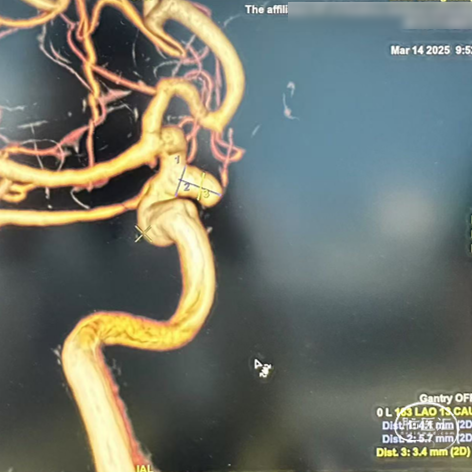

术前影像

右侧颈内动脉3D造影:右侧颈内动脉C6动脉瘤。

右侧颈内动脉造影重建:右侧颈内动脉动脉瘤。